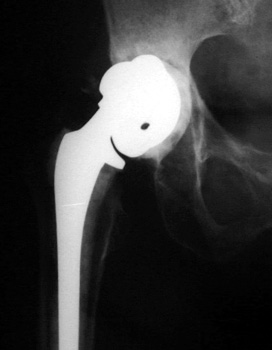

LooseningAs pain and disability due to loosening become severe enough to require revision arthroplasty, abnormalities in the binding of the cement to the bone or prosthesis are almost always visible radiographically. Radiographic abnormalities include:

Absence of these findings requires consideration of other sources for painful arthroplasty. INTERFACE WIDENING

No prior studies available. Abnormally widened interfaces surrounding entire cement mantle of femoral component, consistent with loosening.